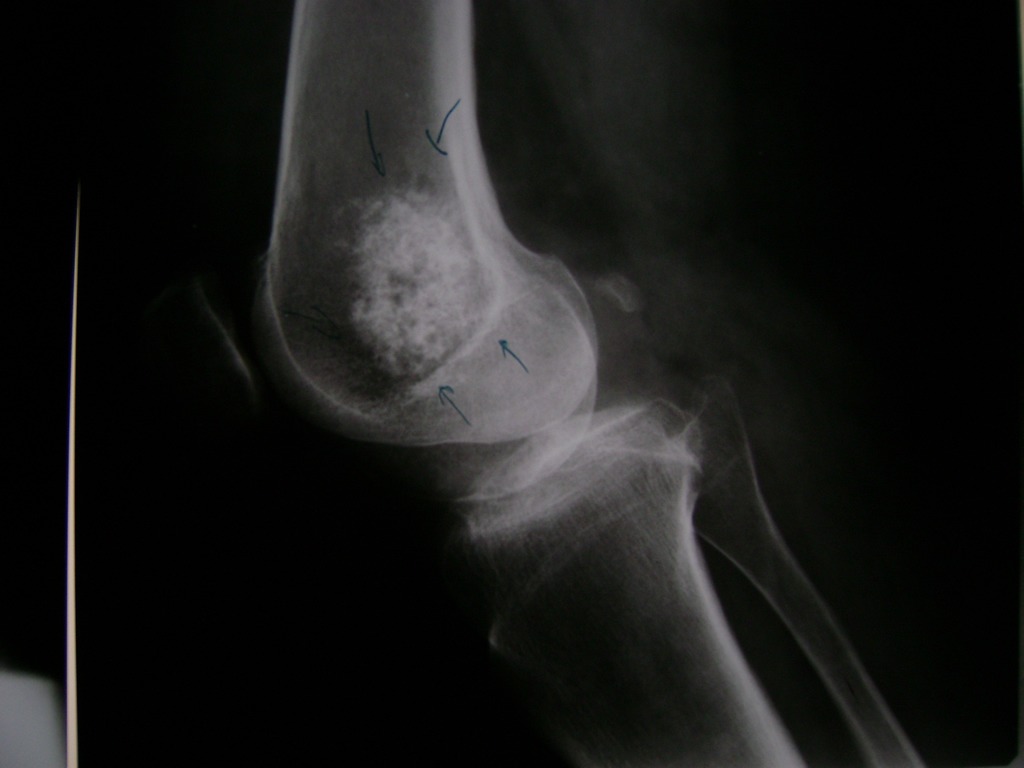

Cirugías de Húmero - Rodilla

La artroscopia de rodilla es un cirugía en el cual la estructura interna de la articulación es examinada ya sea para realizar un diagnostico o para realizar un tratamiento, este procedimiento se realiza utilizando un instrumento parecido a un pequeño tubo llamado artroscopio.